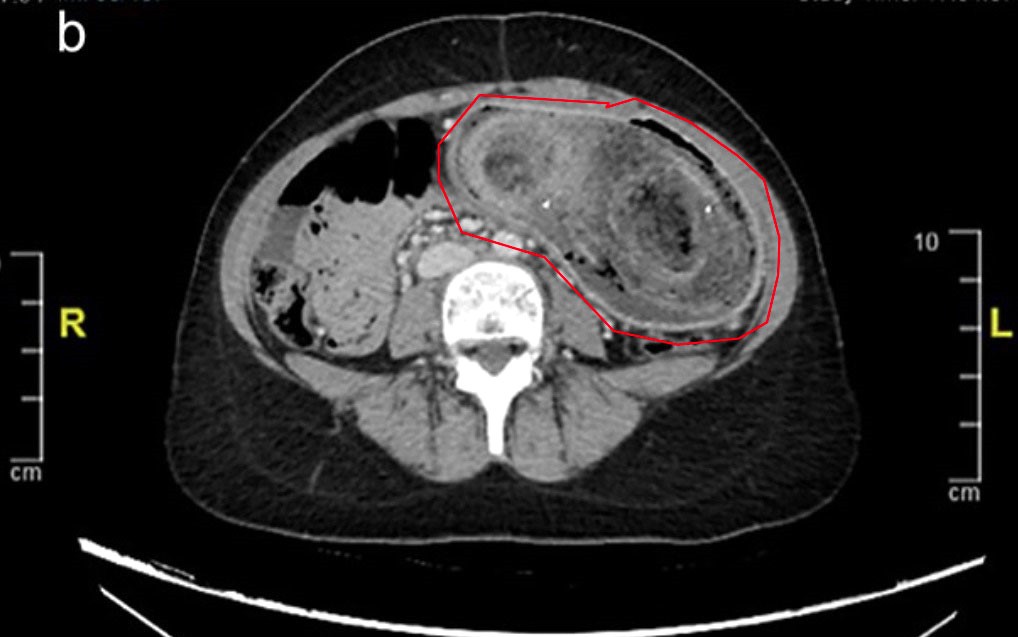

Các bác sĩ đã bối rối cho đến khi chụp CT phát hiện ra dị vật nhỏ có kích thước 3,7 cm, mà họ cho rằng đó là một chiếc xương vô tình nuốt phải từ bữa tối với thịt gà.

Họ đã yêu cầu phẫu thuật nội soi khẩn cấp để tìm hiểu thêm và phát hiện ra nguyên nhân: một chiếc tăm gỗ đã đâm thủng ruột, theo như Need To Know đưa tin .